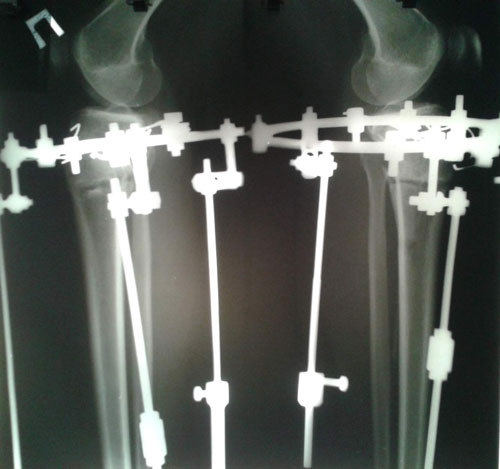

Поздравляю! Ура! Результат отличный!Sekretar Onipko писал(а):Рентген в 58 дней.

Сращение отличное, через неделю снимаем аппараты.

Дата операции 08.10.2015г.

Дата снятие аппаратов 11.12.2015г.

Срок лечения 62 дня.